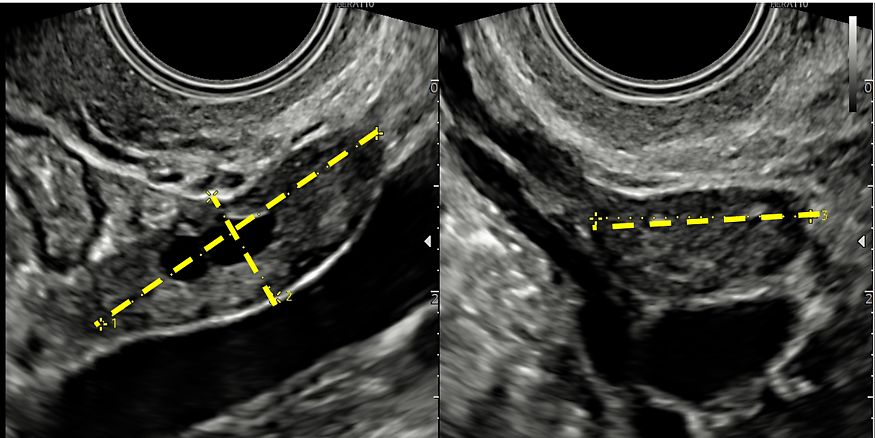

Ultrasound examination of the uterus includes evaluation of its orientation, dimensions (Figure 3), contours and morphology in order to exclude uterine malformations and to detect changes in echostructure of the myometrium due to the presence of benign (e.g. fibroids, adenomyosis) or malignant (e.g. sarcomas) pathology (Video 3). Orientation of the uterus is described in terms of both its version and flexion, where version indicates the relationship between the uterine body and the vagina, and flexion refers to the relationship between the uterine body and the cervix.

3

(a) Longitudinal scan of the uterus with measurements of its anteroposterior and craniocaudal diameters. (b) Transverse scan of the uterus with measurement of its laterolateral diameter.